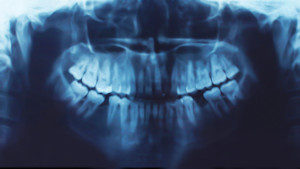

Panorex

The Panorex film provides Dr. Shumway with a panoramic view of the oral cavity and provides information at a glance about existing fillings, supporting bone, sources of infection, tumors, cysts, and decay.

The Panorex film shows more of the mouth and surrounding structures, but with less detail of individual teeth than small films.